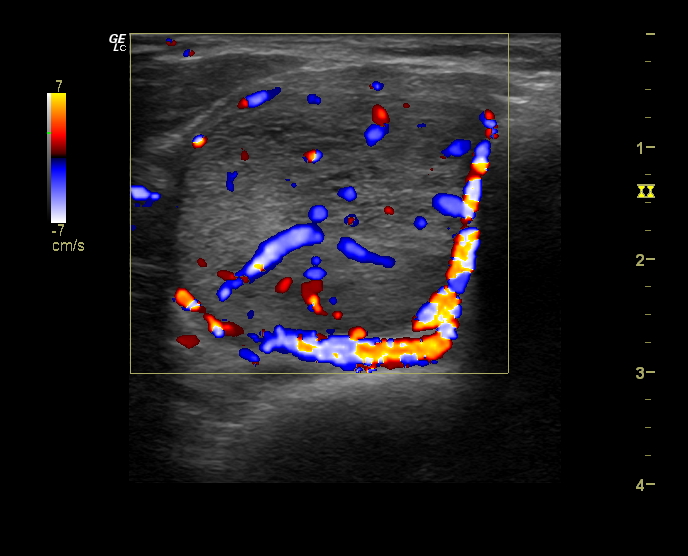

Hallazgos ecográficos

Se estudia la glándula tiroidea mediante sonda lineal de alta frecuencia, realizando cortes transversales y longitudinales. A nivel del lóbulo tiroideo derecho se objetiva un nódulo sólido, con forma «más ancho que alto», isoecoico, con zonas heteroecoicas de 2,4 x 3,4 cm (figura 1), que presenta una lobulación en su margen interno (figura 2), con halo periférico incompleto y vascularización mixta, principalmente periférica (figura 3). No se observan calcificaciones ni adenopatías patológicas. Adyacente al mismo, otro nódulo milimétrico (figura 4), de similares características.